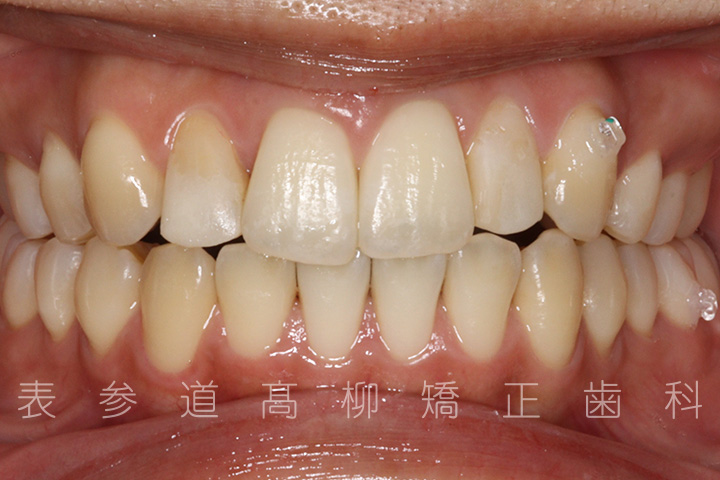

上の前歯が出ているのと前歯が小さいことをお悩みの患者様の症例をご紹介いたします。

・上顎前突(前歯の前方傾斜)

・2⏊2矮小歯(先天的に形態が小さい歯)

・上下前歯部叢生(凸凹歯並び)

術前術後の比較